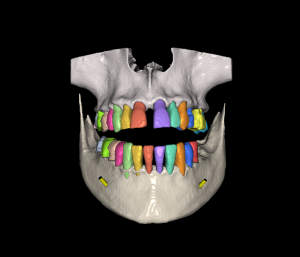

Diseño y colocación de implantes

Diseño y colocación de implantes / Fabricación de guía quirúrgica

Técnica Doble Dicom / Técnica Dicom Stl

Técnica Doble Dicom

Técnica Dicom Stl